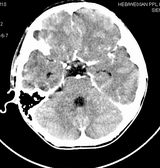

男,10岁,因近来常头痛就诊。先平扫拟诊右侧脉络膜裂囊肿,后薄层(3mm)扫描见此灶与右侧脑室后角相通,且向内几乎与鞍上池相连,并见一血管影沿其走形 (可能是脉络膜前动脉)。1。请教:脉络膜裂或脉络膜裂囊肿与侧脑室颞角或鞍上池相通吗?好像谁说脉络膜裂是脉络膜从外侧裂向侧脑室移行的裂隙。请高手讲讲这点的解剖关系。2。建议:对于老年患者,有丘脑附近特别是右丘脑附近的近似腔隙性梗死灶,临床症状不明显的,应做3mm薄层扫描,看病灶向下是否与侧脑室颞角相连,以免误诊。

薄层强化: